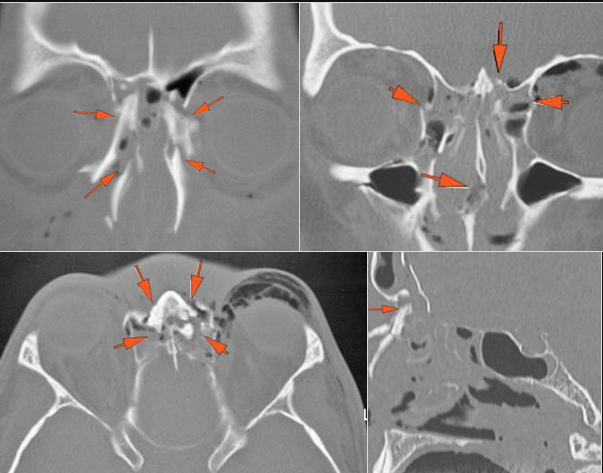

There is evidence of a subperiosteal hematoma along the medial or lateral wall, roof or floor of the orbit.

The circumferential extraconal and the intraconal orbital fat are infiltrated.

There is evidence of herniated intra-orbital fat.

There is evidence of bony injury along the walls and/or floor of the orbit.

There is bony injury of the orbital roof or related portions of the frontal bone.

The optic strut and remainder of the optic canal and adjacent body and lesser wings of the sphenoid bone are fractured.

There is a fracture of the greater or lesser wing of the sphenoid bone or basisphenoid.

The mesial naso-orbito-ethmoid complex is fractured. Specifically, there is bony injury of the nasal bones or the frontal process of the maxilla and the medial walls of the orbit are abnormal.

There is injury of the ethmoid complex. Specifically, the ethmoid roof, olfactory fossa and the cribriform plate are fractured and/or significantly dehiscent.

The frontal bone and frontal sinus inner and outer tables are fractured.